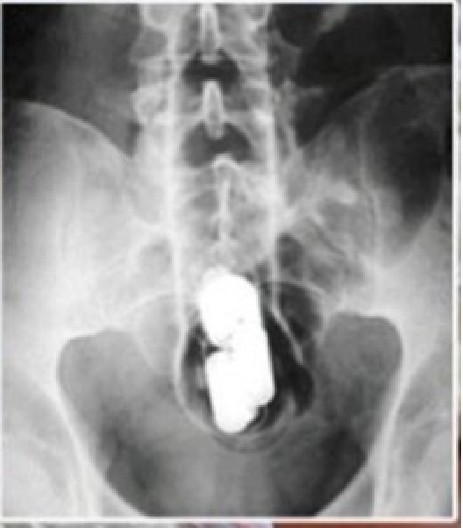

Kao jedan od ključnih dokaza na sudu poslužio je rezultat ginekološkog pregleda i rendgenski snimak stomaka uhapšene na kojem se videlo da je heroin upakovala u prezervativ, a zatim ga gurnula u vaginu.

Box: Image

„Dovitljiva“ dilerka uhapšena je u februaru 2010. godine.